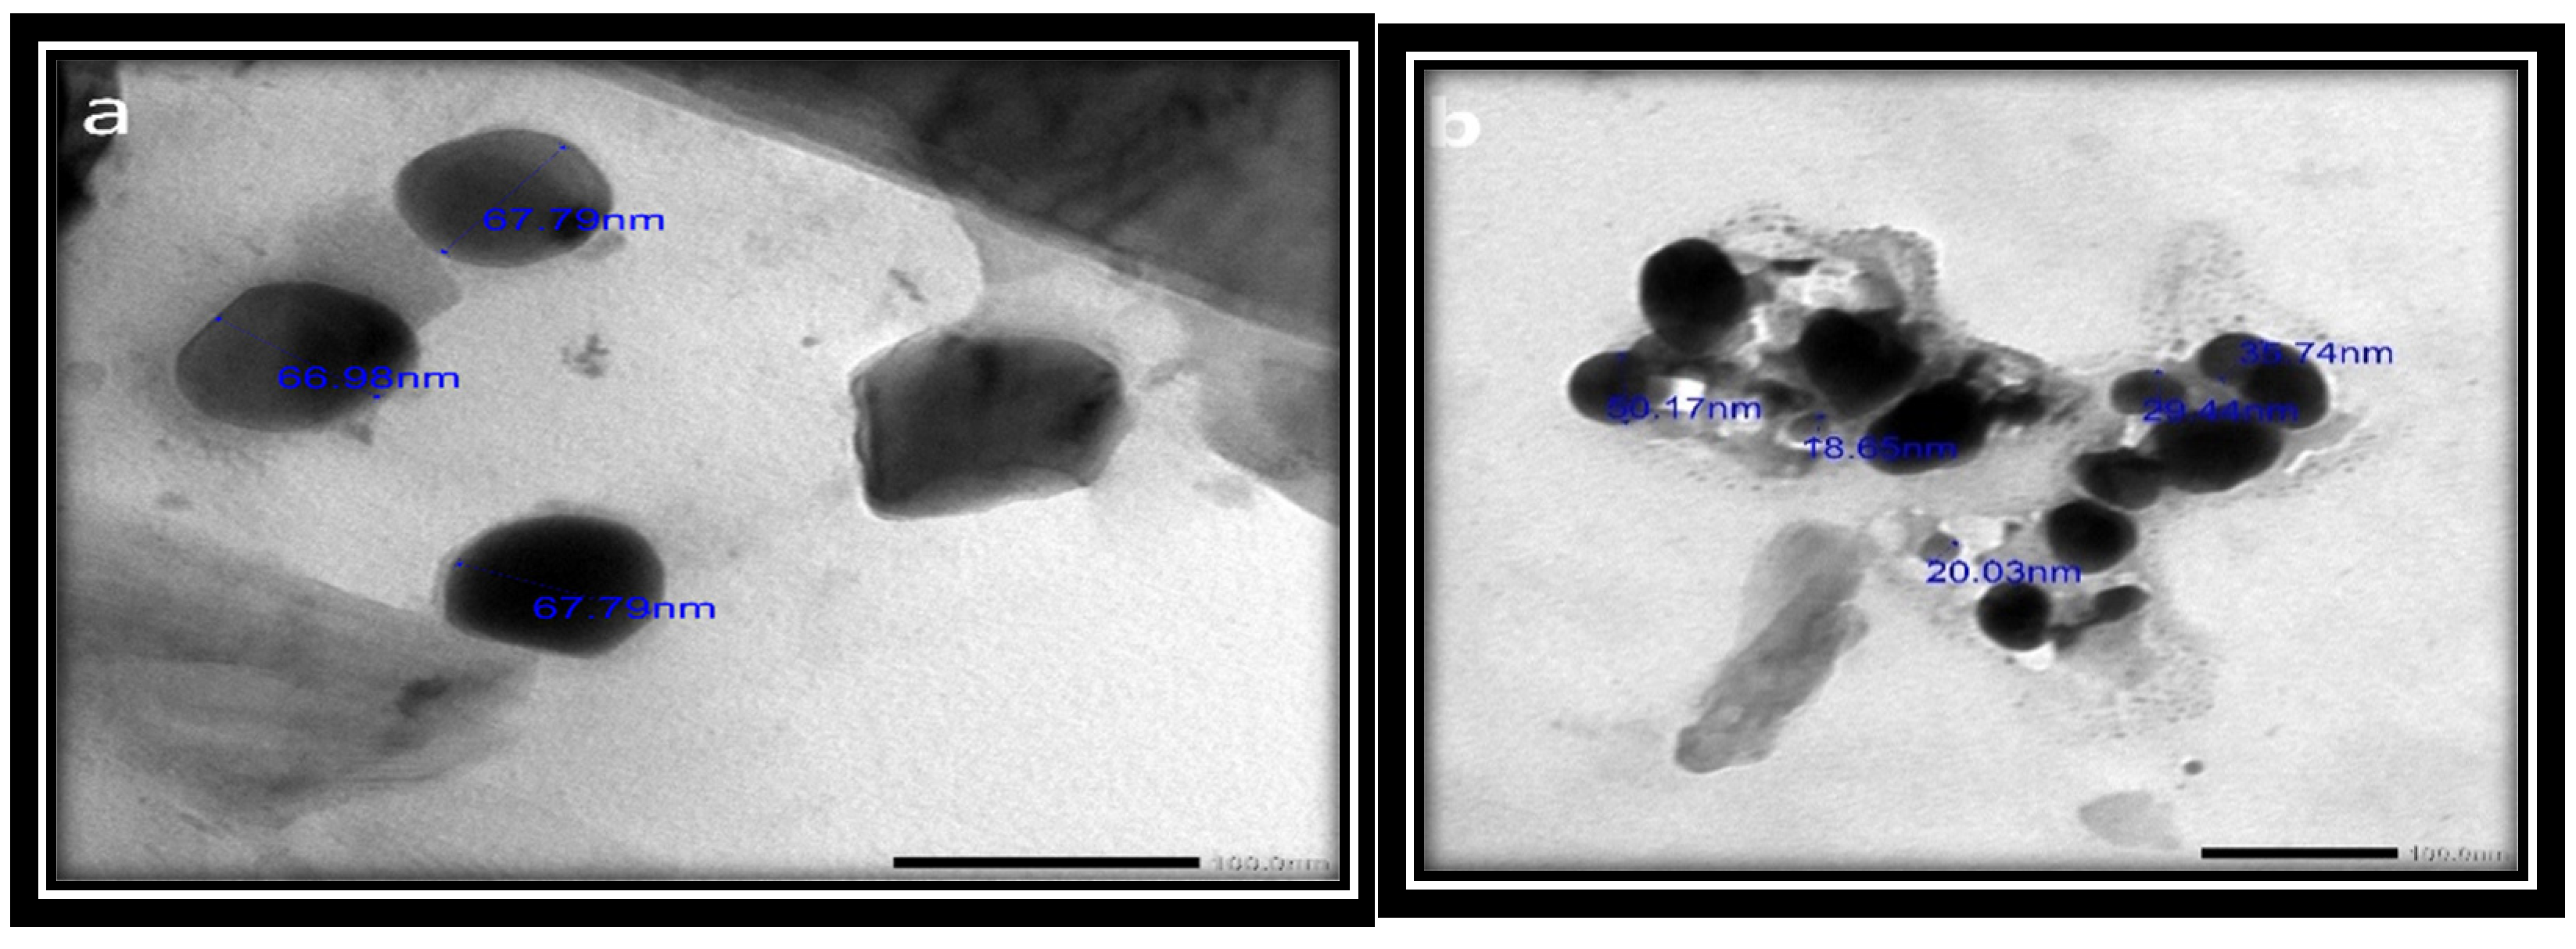

3.2.4. TEM Imaging